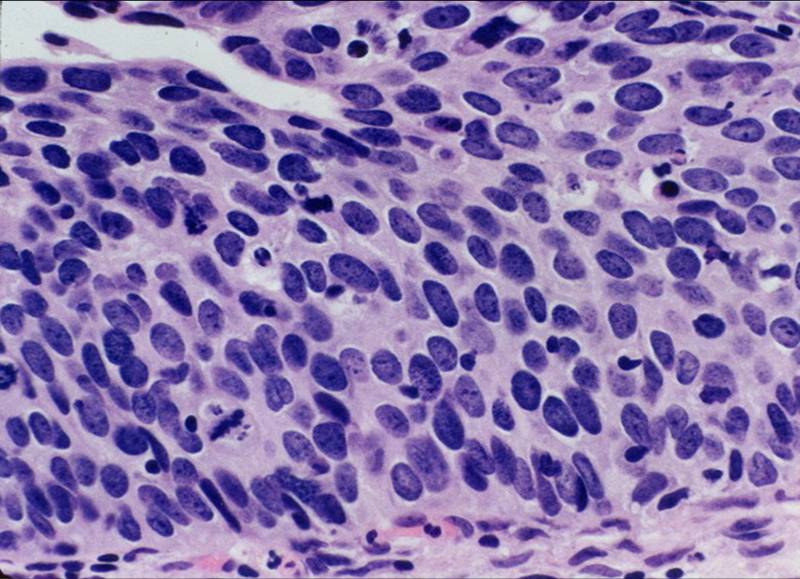

TBS-40.CIN 3 切片